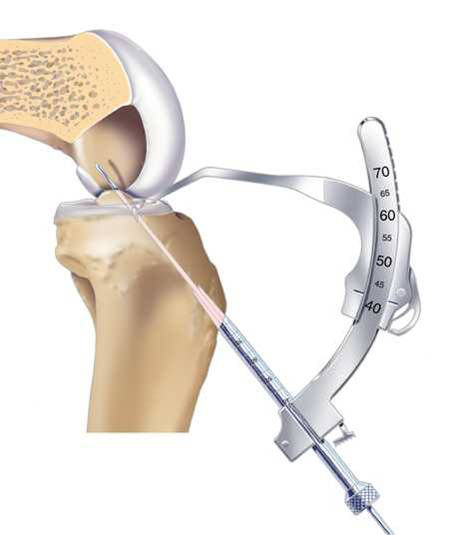

關(guān)節(jié)鏡手術(shù)專用器械

脛骨點(diǎn)選取

股骨點(diǎn)

Rigidfix固定

Intrafix固定